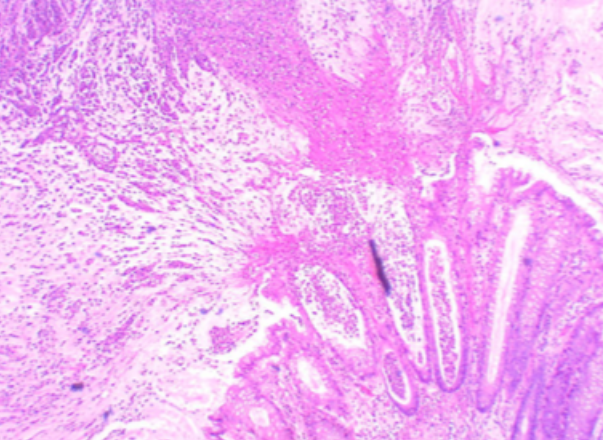

75yo male with heavy smoking and alcohol histories presents with progressive dysphagia and weight loss

Oesophageal cancer (SCC)